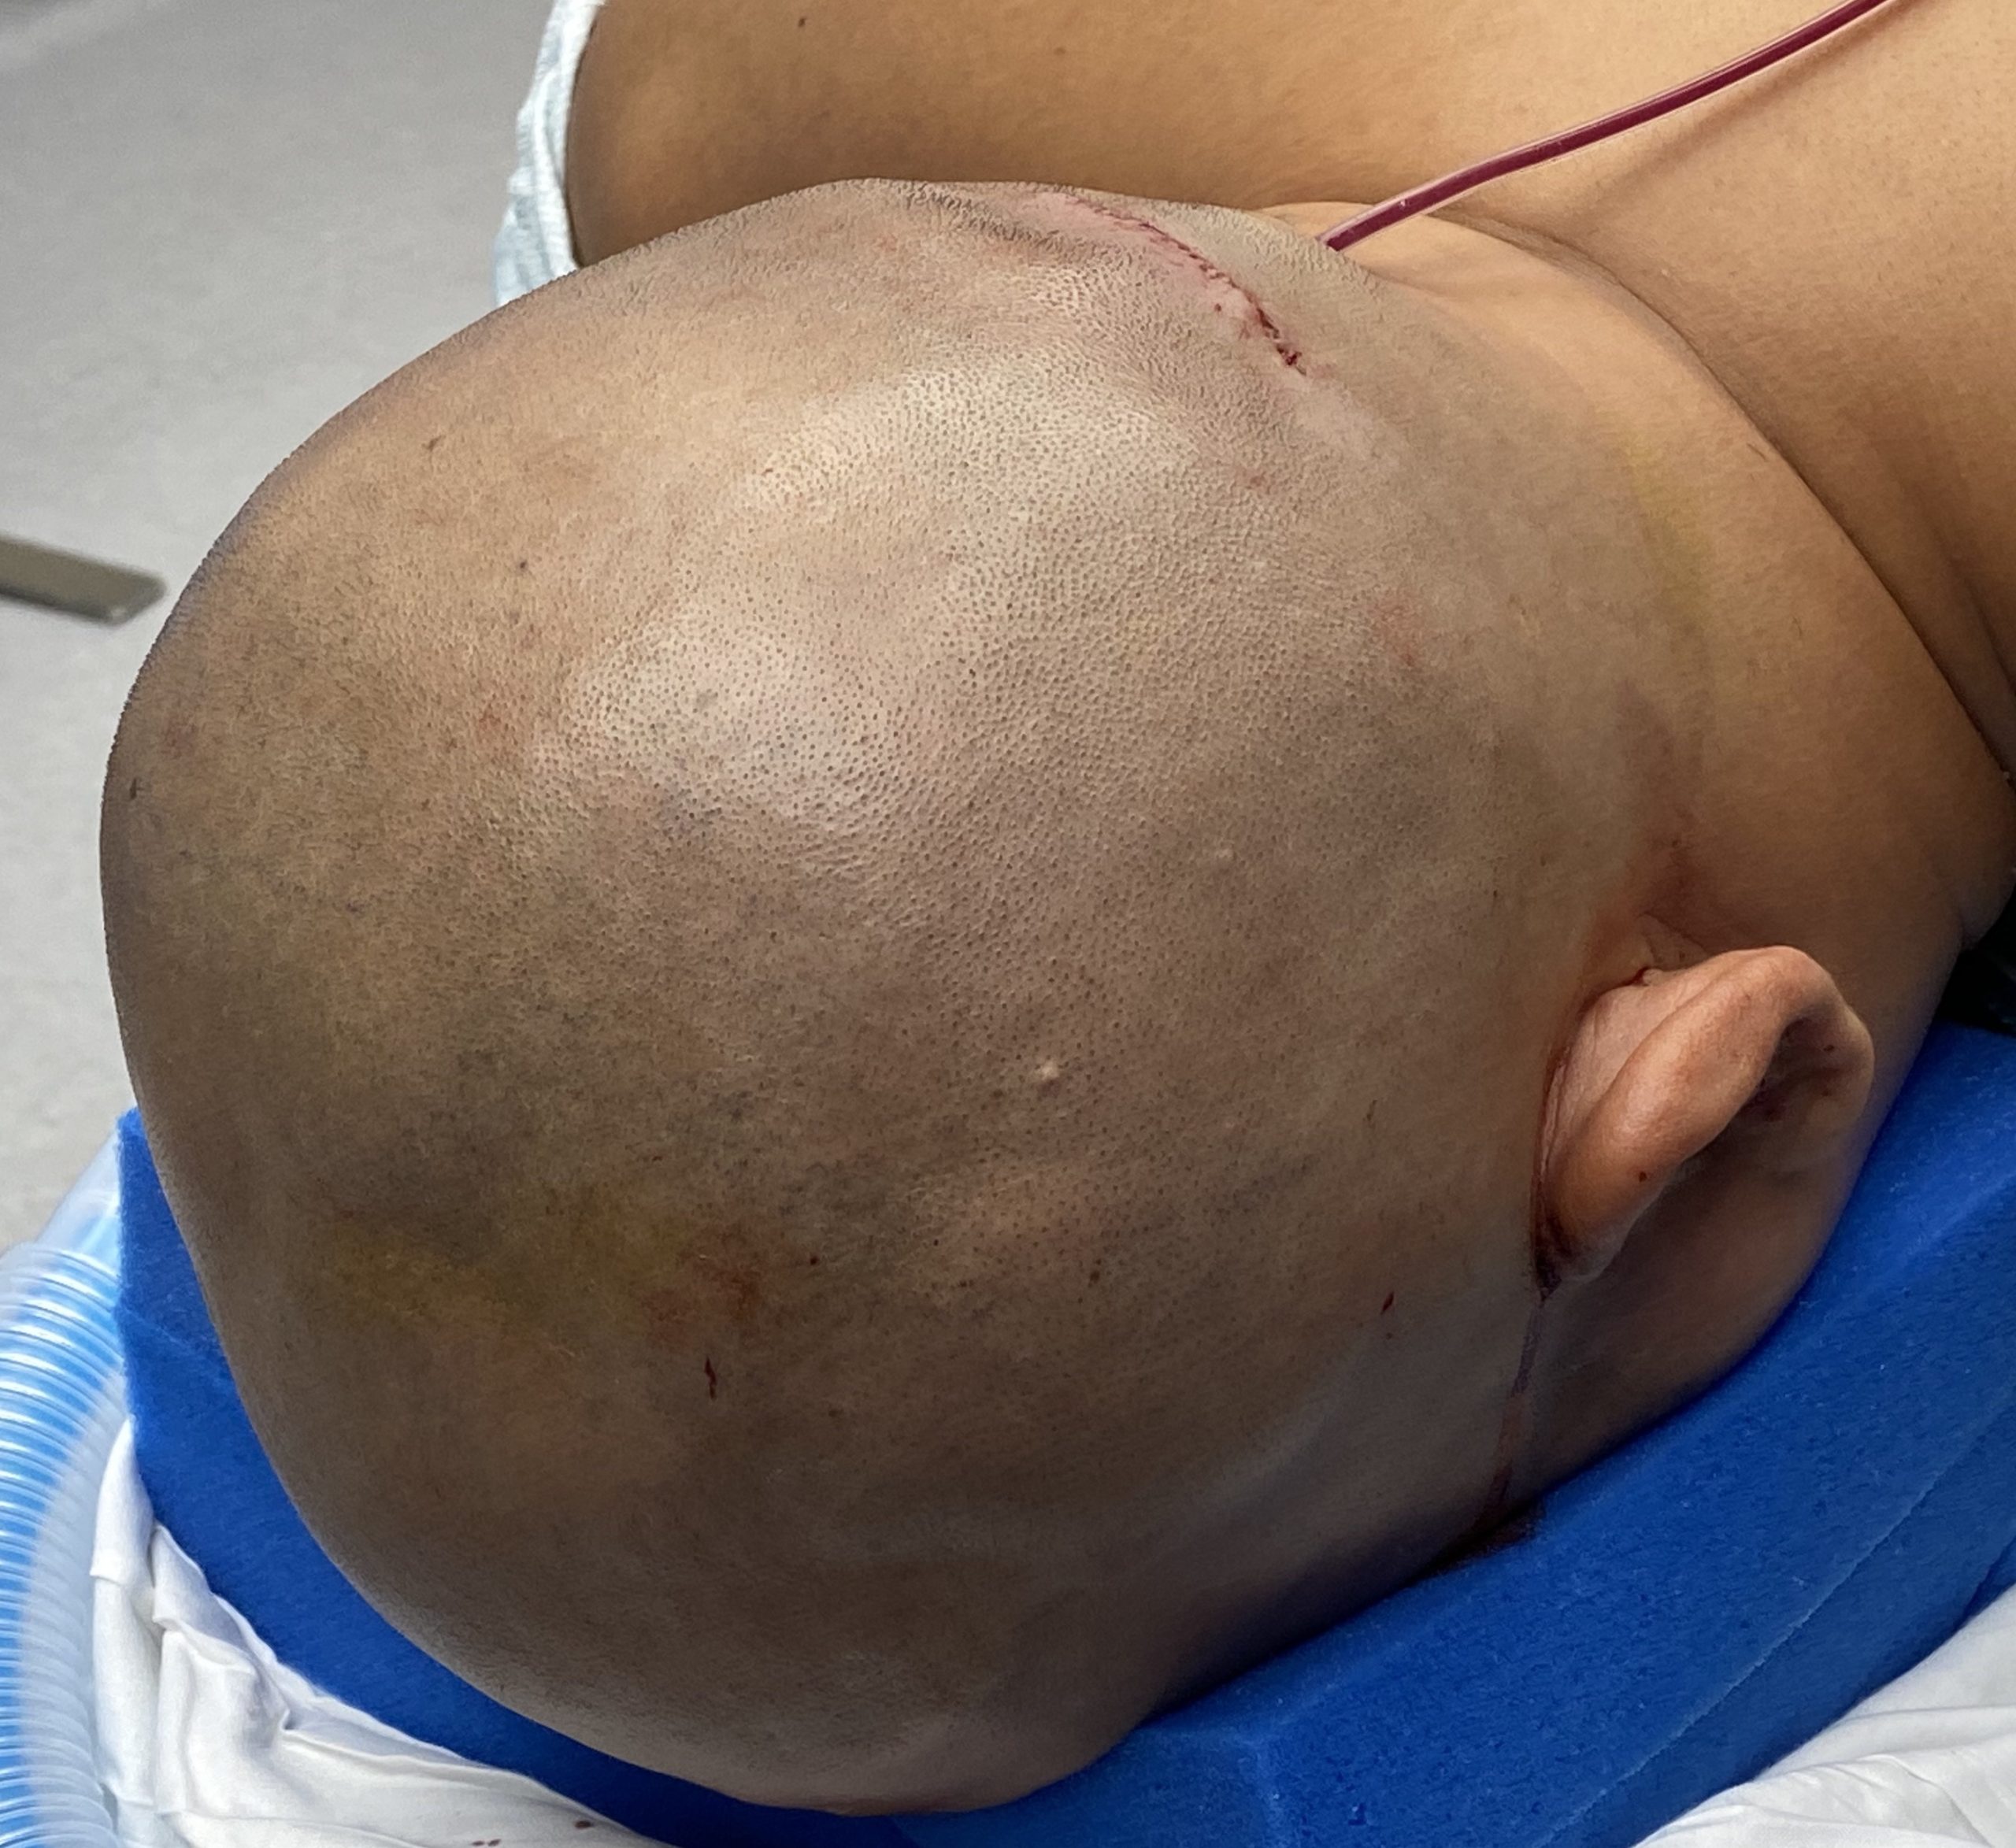

Patient 51

Desire for taller and rounder head shape.

Two stage custom skull implant augmentation technique.

Desire for taller and rounder head shape.

Two stage custom skull implant augmentation technique.